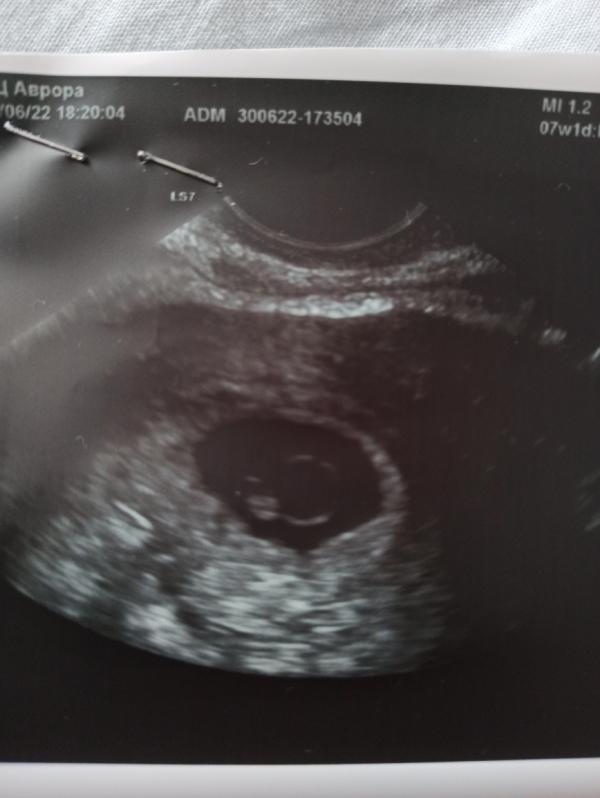

Девочки, нужна поддержка и совет! Т.к. о моей беременности знаю только я и мой врач, то скоро сойду с ума! Рассказать пока ни кому не могу. И так - в 6 акушерских недель мне сделали УЗИ, эмбриона не было и поставили анэмбрионию (свд=15)… сказали переделать через неделю. Сегодня 7 недель (акушерских) четко увидели эмбрион 4 мм свд=20, но сердцебиение не слышно было. Теперь ставят замершею беременность. Потому что на этом сроке должно бится сердце. Уже можно расстраиваться или еще рано? У кого так было напишите пожалуйста! И чем закончилось.